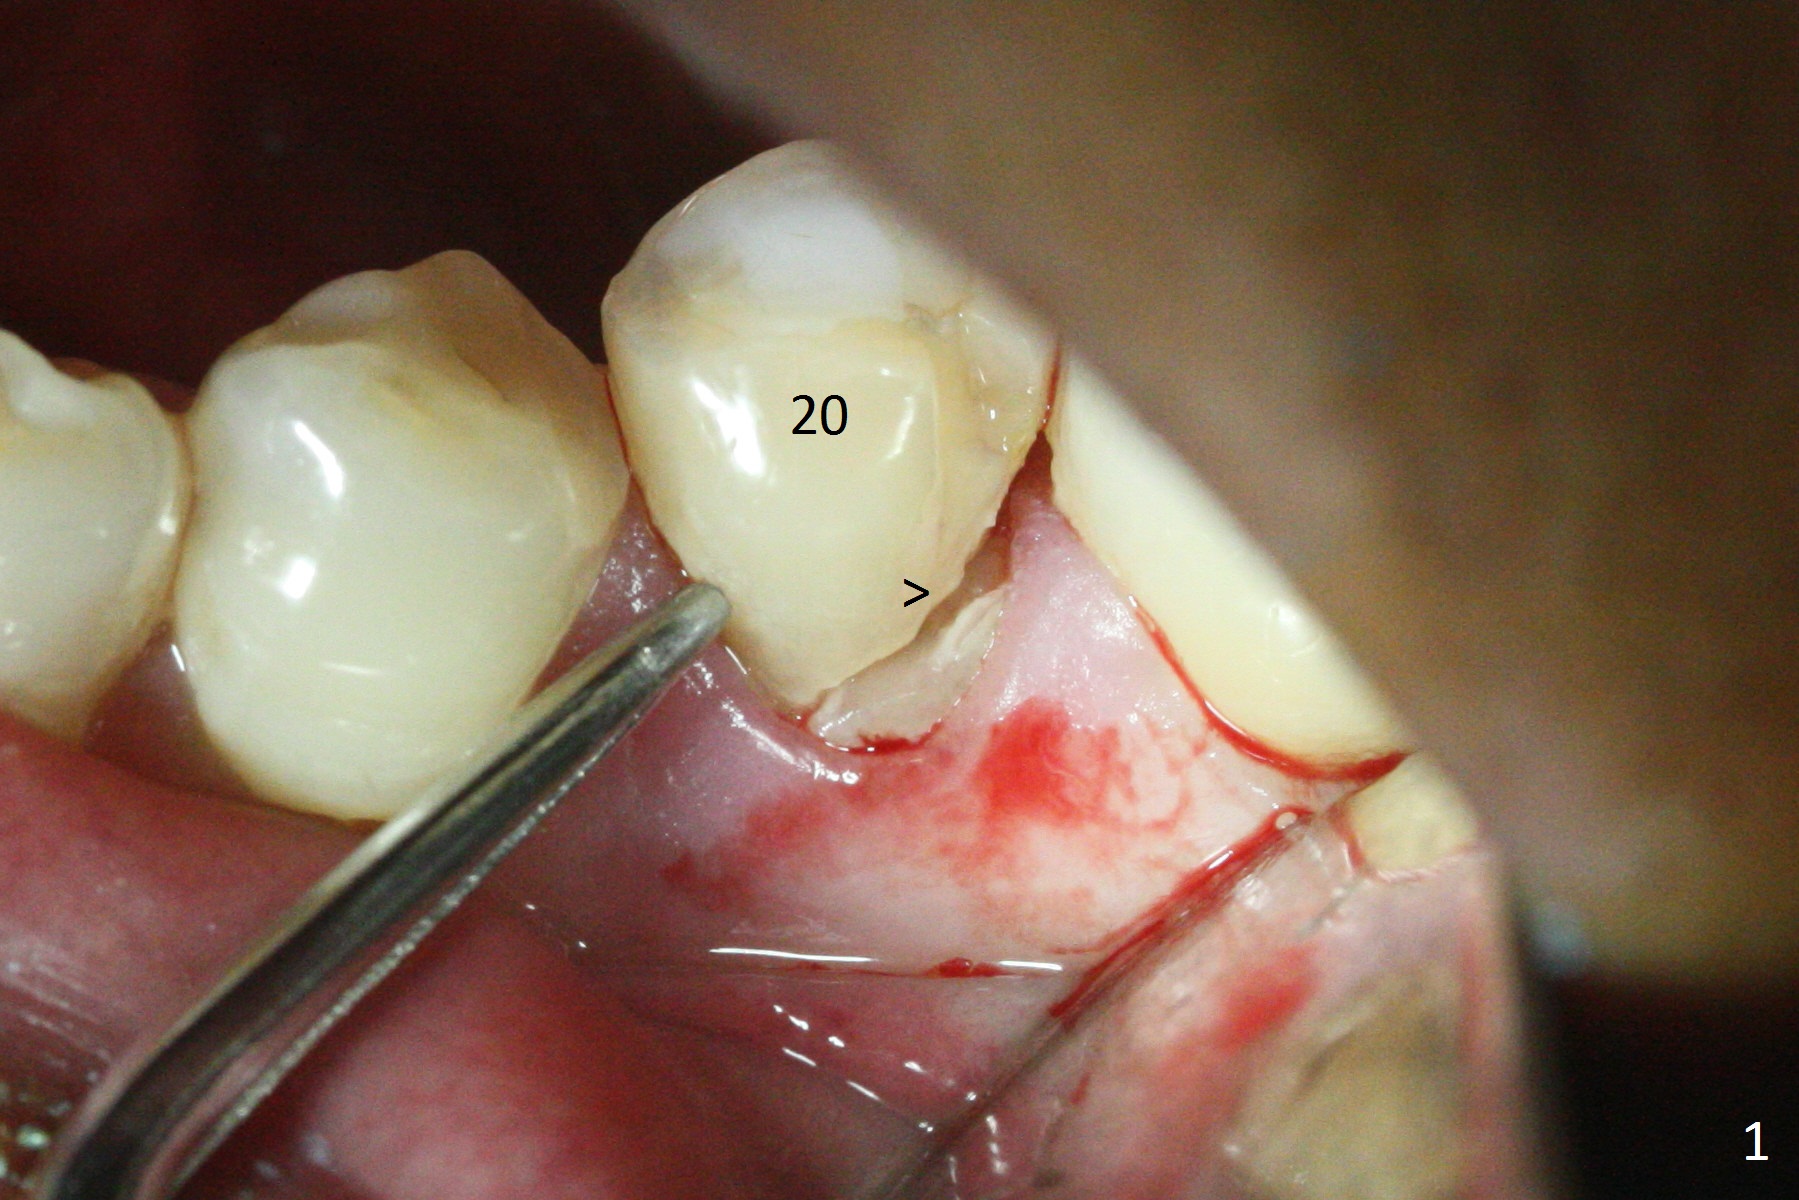

Extraction of the lower left 2nd premolar with vertical fracture (Fig.1,2 >) is easy because of peri-radicular radiolucency. The apical end of the osteotomy is not shown with a 2 mm pilot drill (Fig.3) or a 3.8x18 mm implant (Fig.4) in place. It appears that the implant is not placed deep enough. Following 3-4 more turns of the implant and placement of a 5.5x4(3) mm abutment (Fig.5 A), allograft is placed (*). A postop panoramic X-ray is taken (Fig.6); the osteotomy could have been deepened to reduce the possibility of periimplantitis. Retrospectively, the panoramic X-ray should be taken after use of the pilot drill. The bone around the implant appears to have regenerated 4 months postop (Fig.7,8). Bone density appears to continue increasing 9 months postop (i.e., 4.5 months post cementation, Fig.9). Bone loss is minimal 2 years post cementation (Fig.10).